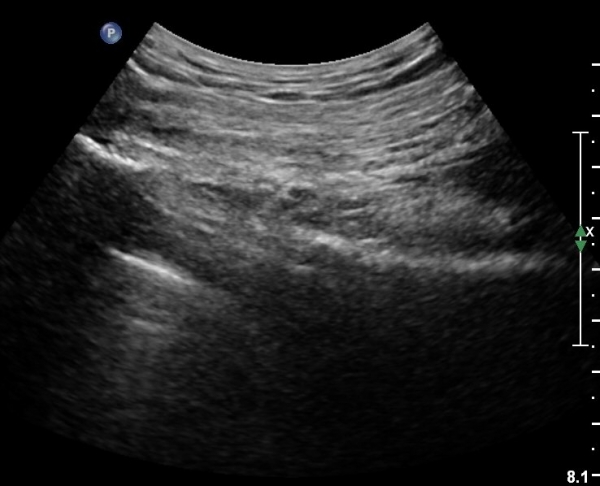

ŽÃÊÀÚ¸¦ ¾à°£ ¾Æ·¡·Î À̵¿Çϸé Á°ñÀÇ ¸ð¾çÀÌ º¼·ÏÇÑ ¸ð¾ç¤·¿¡¼­ ¼öÆòÇÏ°Ô °üÂûµÇ´Âµ¥ ÀÌ ±¸Á¶¹°Àº Á°ñ±Ø(ischial spine)À̰í ÀÌ À§Ä¡¿¡¼­ ŽÃËÀÚ¸¦ Á¶±Ý¾¿ ±â¿ï¿©¼­ °üÂûÇϸé Á°ñ±Ø ³»Ãø°ú ¿¬°áµÇ´Â °í¿¡ÄÚ ¶ì ¸ð¾ç ±¸°í¹°ÀÌ °üÂûµÇ´Âµ¥ À̰ÍÀÌ Ãµ°ñ°¡½Ãµ¹±â ÀδëÀÌ´Ù. ÀÌ Àδë Ç¥Ãþ¿¡¼­ õ°ñ°áÀýÀδ븦 °üÂûÇÒ ¼ö ÀÖ°í ÀÌ µÎ ÀδëÀÇ »ç¿¡¼­ À½ºÎÅë¸ÆÀ» °üÂûÇÒ ¼ö ÀÖ°í À½ºÎµ¿¸Æ ³»Ãø¿¡¼­ À½ºÎ½Å°æ(pudendal nerve)¸¦ È®ÀÎÇÒ ¼ö ÀÕ´Ù(»çÁø 8, 9).